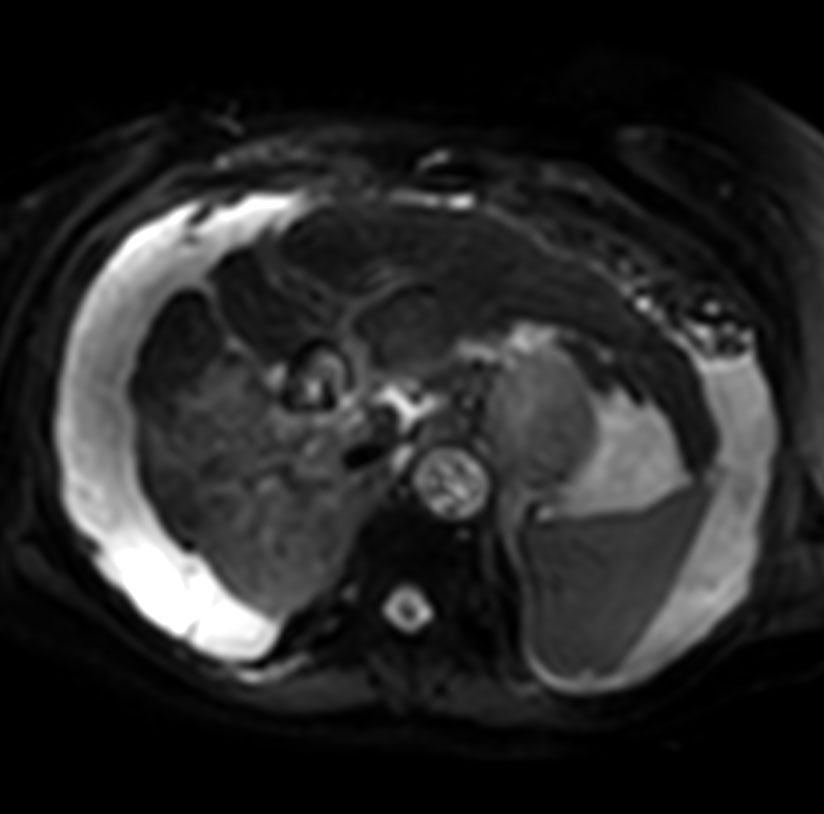

Axial Diffusion - b50